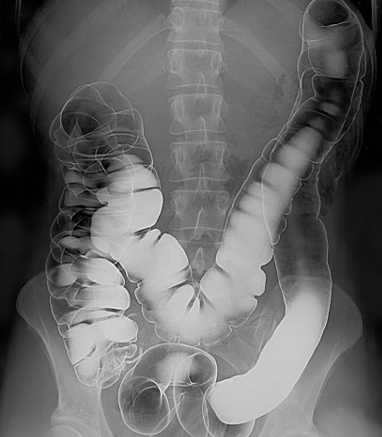

A barium enema is a rectal injection of barium contrast. This coats the lining of the colon and rectum and X-ray films are obtained under fluoroscopic control. Air introduced into the large bowel may be used to give a double-contrast technique. Barium enemas are performed much less often than in the past because of the increasing use of colonoscopy and CT colonography.

Intestinal tract barium enema

By Glitzy queen00 at English Wikipedia., Public domain, via Wikimedia Commons

Barium is run into the colon under gravity and radiographs are taken. Air is also then introduced into the rectum for a double-contrast barium enema.